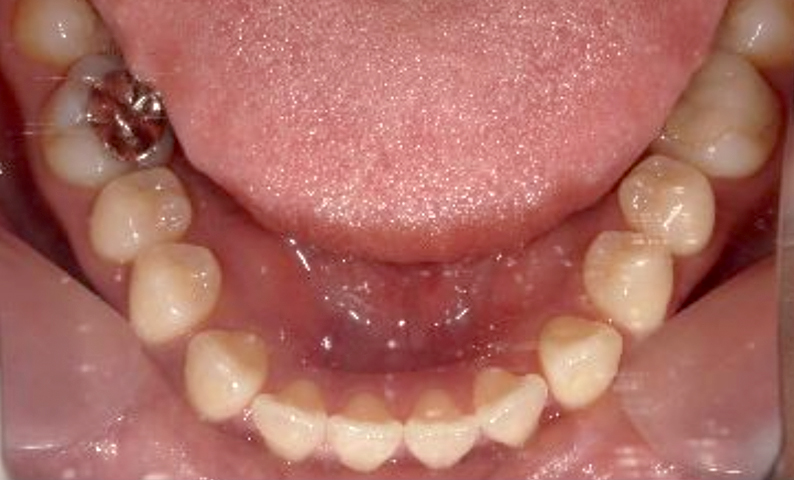

| 治療前 | 治療後 |

|---|---|

|